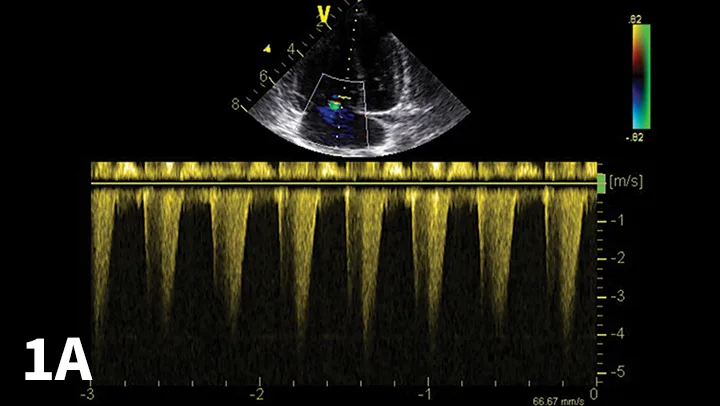

Abdominal ultrasonography is helpful to evaluate the patient for other underlying conditions and to evaluate the hepatic vessels (Figure 3).

Abdominal ultrasound image documenting enlarged hepatic vessels consistent with right-sided heart failure.